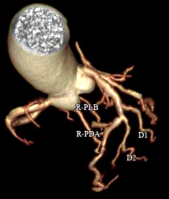

Công nghệ tim mạch Aheart

Khám phá nhiều hơn, đi sâu vào từng chi tiết

Công nghệ DE tiên tiến: Tích hợp đa dạng kỹ thuật năng lượng kép, hình ảnh rõ nét

Phân tích toàn diện: Cung cấp đồng thời đánh giá định tính và định lượng chuyên sâu.

Giá trị lâm sàng vượt trội: Hỗ trợ nâng cao độ tin cậy trong chẩn đoán và điều trị.

Hình ảnh lâm sàng